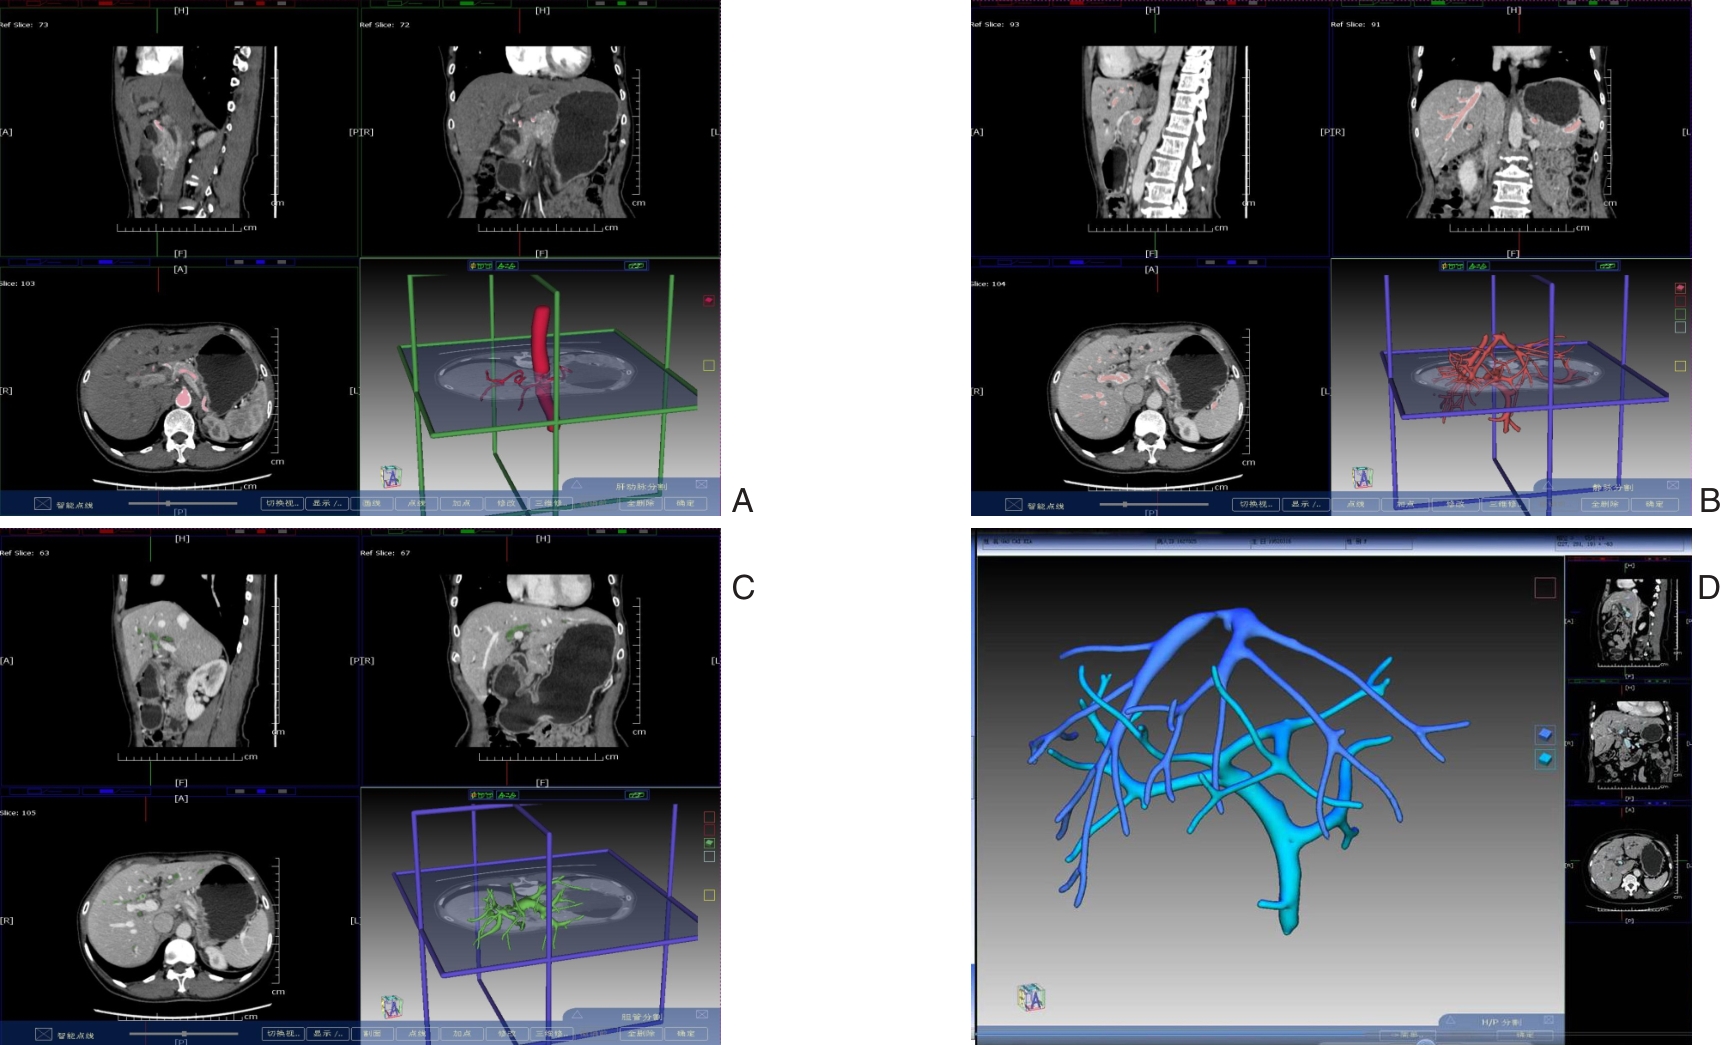

• Clinical application of three-dimensional visualization technology in assessing the spatial configuration of major hepatic vessels and liver lobar volume distribution

2026, 35(1):124-140. DOI: 10.7659/j.issn.1005-6947.250635

Abstract (93) HTML (137) PDF 3.82 M (171) Comment (0) Favorites

Abstract:Background and Aims The hepatic vascular and biliary systems exhibit substantial anatomical variability and complex spatial relationships, posing challenges for precise surgical planning based on conventional two-dimensional imaging. This study aimed to evaluate the clinical value of three-dimensional visualization in characterizing the spatial architecture of hepatic vasculature and bile ducts and to explore its association with hepatic volumetric distribution.Methods A total of 610 living liver donors and 158 patients with bile duct dilatation were retrospectively analyzed. Three-dimensional models of the hepatic artery, portal vein, hepatic veins, and bile ducts were reconstructed from contrast-enhanced CT images. Vascular and biliary anatomical patterns, spatial relationships, and their correlations with hepatic lobe and segmental volumes were systematically assessed.Results Three-dimensional visualization enabled intuitive and comprehensive depiction of hepatic vascular and biliary anatomy. Distinct portal vein configurations were associated with significant differences in regional liver volume distribution, with an increased proportion of the right posterior lobe observed in patients with specific portal vein branching patterns. The presence of an inferior right hepatic vein with a diameter ≥5 mm was also associated with a larger right posterior lobe volume. Analyses of extrahepatic and intrahepatic spatial relationships revealed relatively consistent positional patterns between the right hepatic artery, portal vein, and bile ducts, and a significant correlation was observed between the spatial courses of the right hepatic artery and the right posterior bile duct.Conclusion Three-dimensional visualization provides accurate preoperative assessment of hepatic vascular and biliary anatomy and clarifies complex spatial relationships and their volumetric implications. This technique offers critical anatomical support for precision hepatobiliary surgery and liver transplantation.